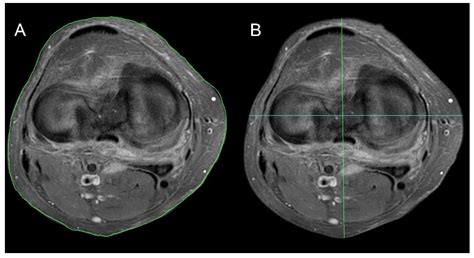

If you have recently experienced persistent joint pain, instability, or a specific injury, your healthcare provider may have recommended a diagnostic scan to get a clearer picture of what is happening inside your joint. Knee MRI images are the gold standard in diagnostic imaging for soft tissue injuries, providing incredibly detailed views that X-rays simply cannot match. Unlike X-rays, which primarily show bone structure, magnetic resonance imaging (MRI) uses powerful magnets and radio waves to create cross-sectional images of the ligaments, tendons, cartilage, and muscles that stabilize your knee. Understanding what these images show and why they are necessary can help demystify the diagnostic process and prepare you for your appointment.

Interpreting knee MRI images is a skill reserved for radiologists, who analyze the scan and produce a detailed report for your referring physician. However, having a basic understanding of what they are looking for can help you better understand your diagnosis. Radiologists look for changes in signal intensity; healthy tissue typically appears in a predictable pattern, while injured or diseased tissue will show up as "brighter" or "darker" areas, known as signal abnormalities.

• mri knee axial anatomy

• knee muscles mri anatomy